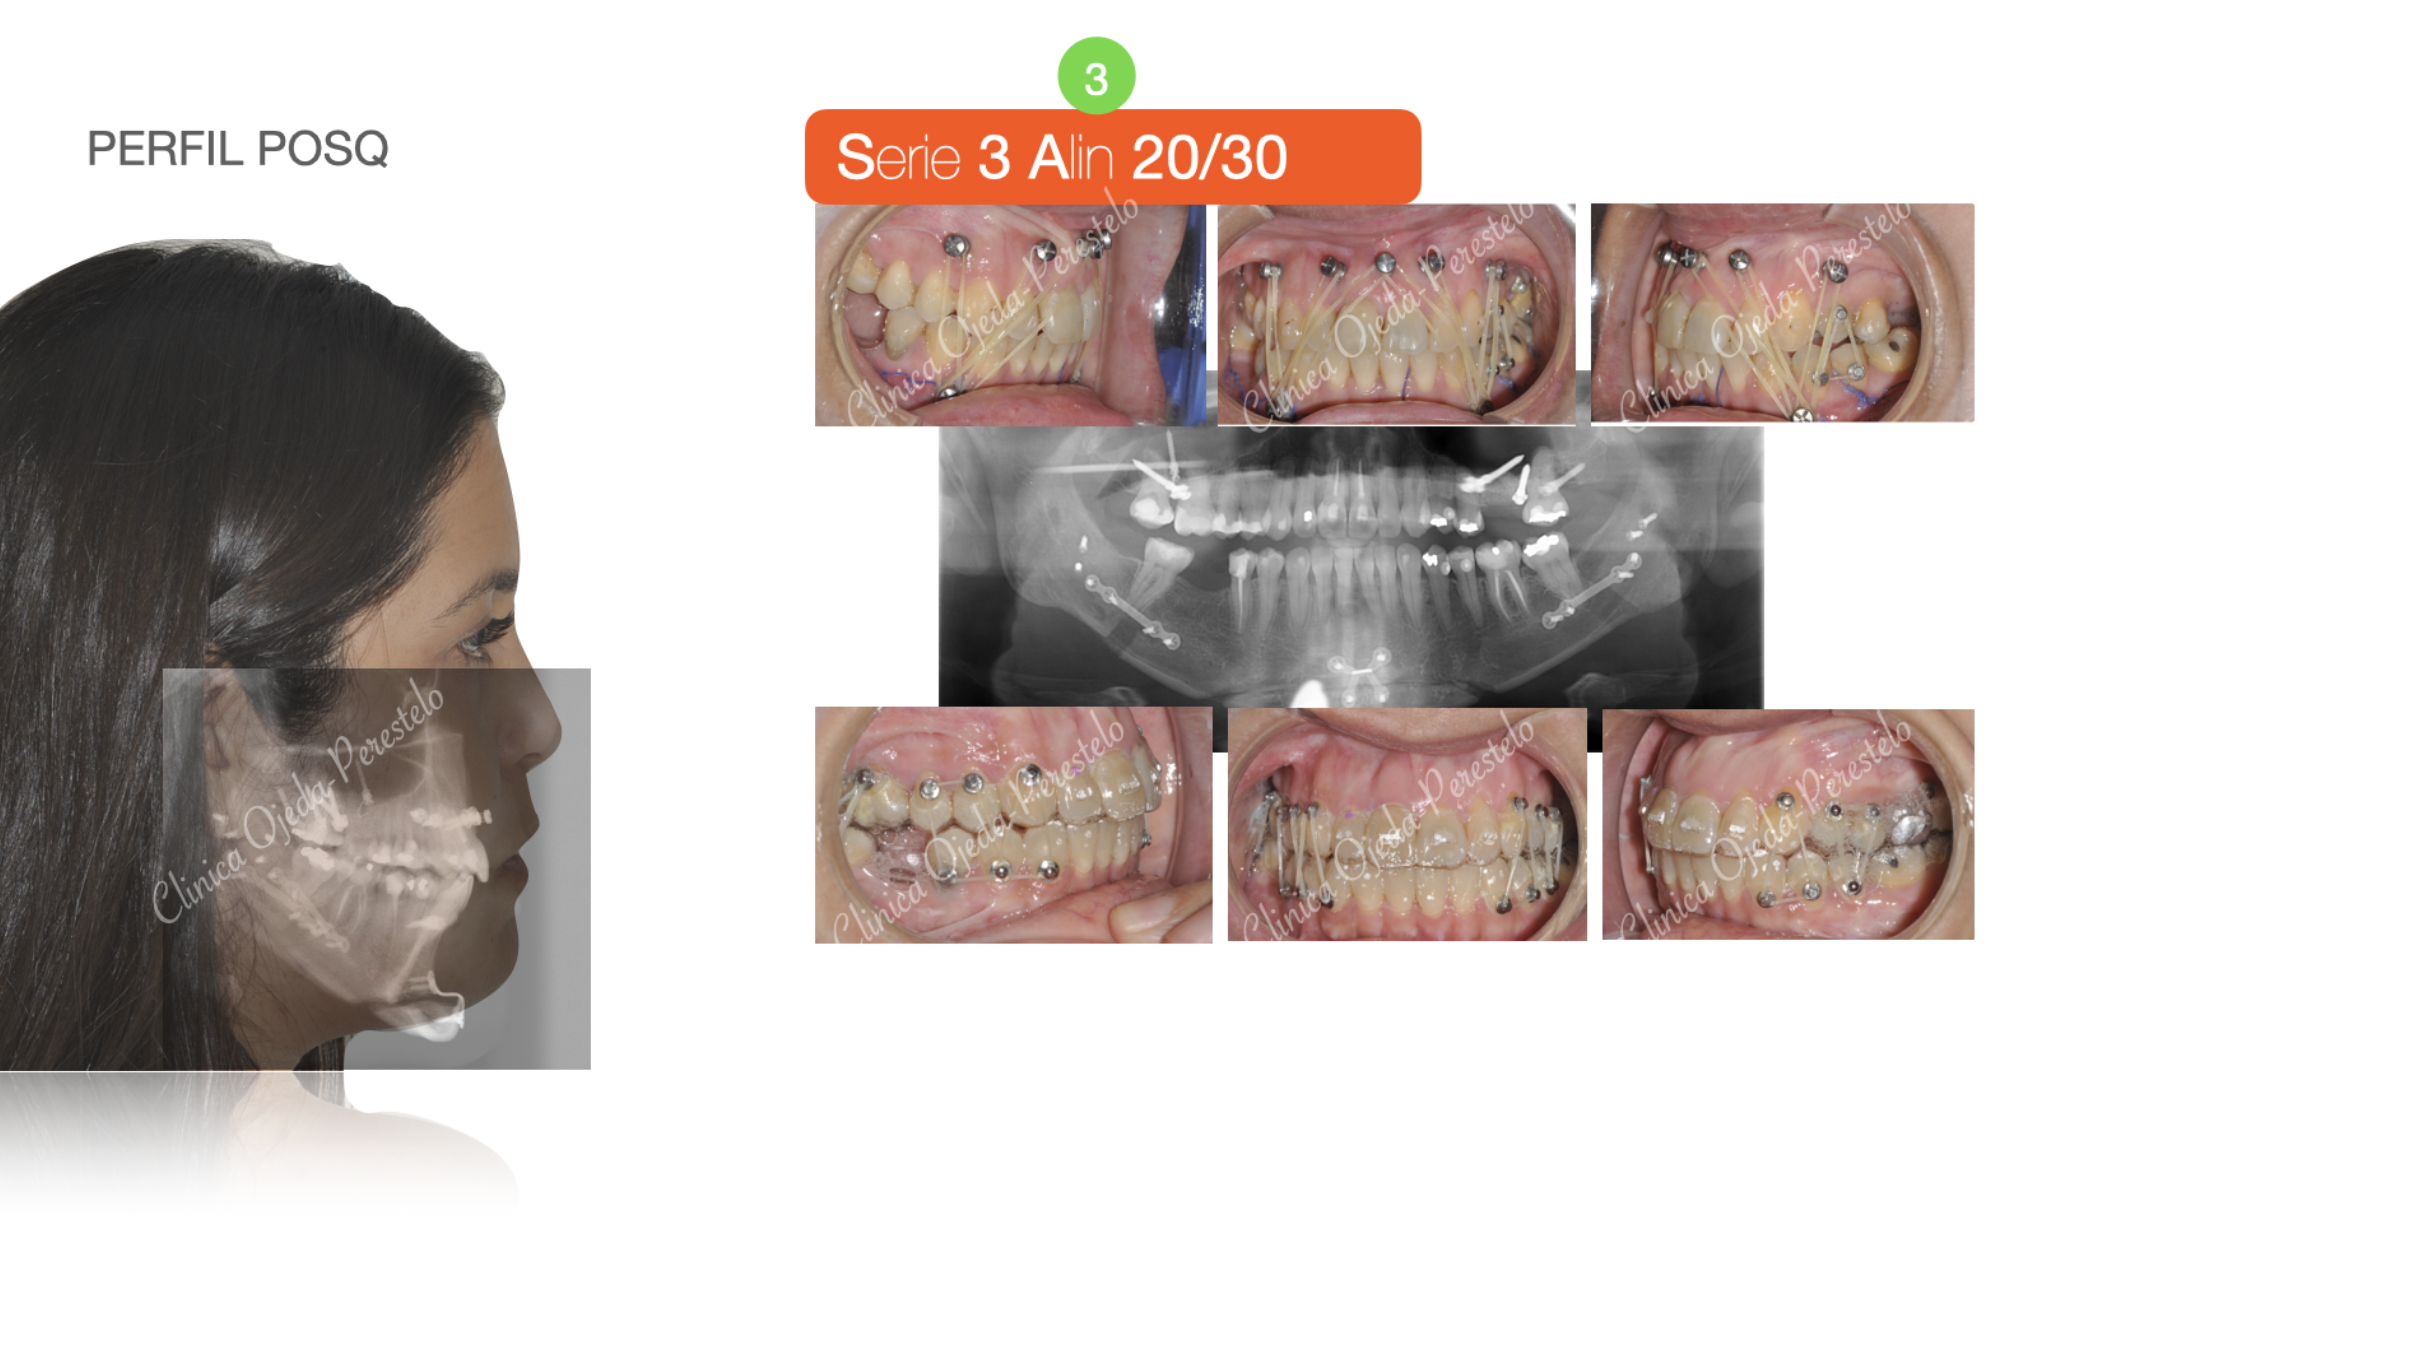

-2. Alineación/Nivelación II+ Cierre de Mordida para Optimización Q. de los Maxilares

-3. Osteotomía Sagital de Rama + Mentoplastia de Aumento. (Dr Nestor Naranjo)